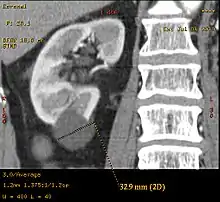

| Renal cyst | |

A renal cyst is a fluid collection in or on the kidney. There are several types based on the Bosniak classification. The majority are benign, simple cysts that can be monitored and not intervened upon. However, some are cancerous or are suspicious for cancer and are commonly removed in a surgical procedure called nephrectomy.